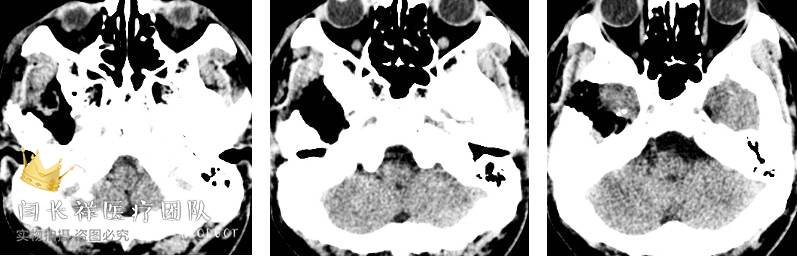

中颅窝-颞下窝占位

术前MRI轴位T1扫描示病灶呈等信号。

术前MRI轴位T2扫描示病灶侵及面神经膝段及中耳骨质。

术前MRI轴位T1增强示病灶显著不均匀强化。